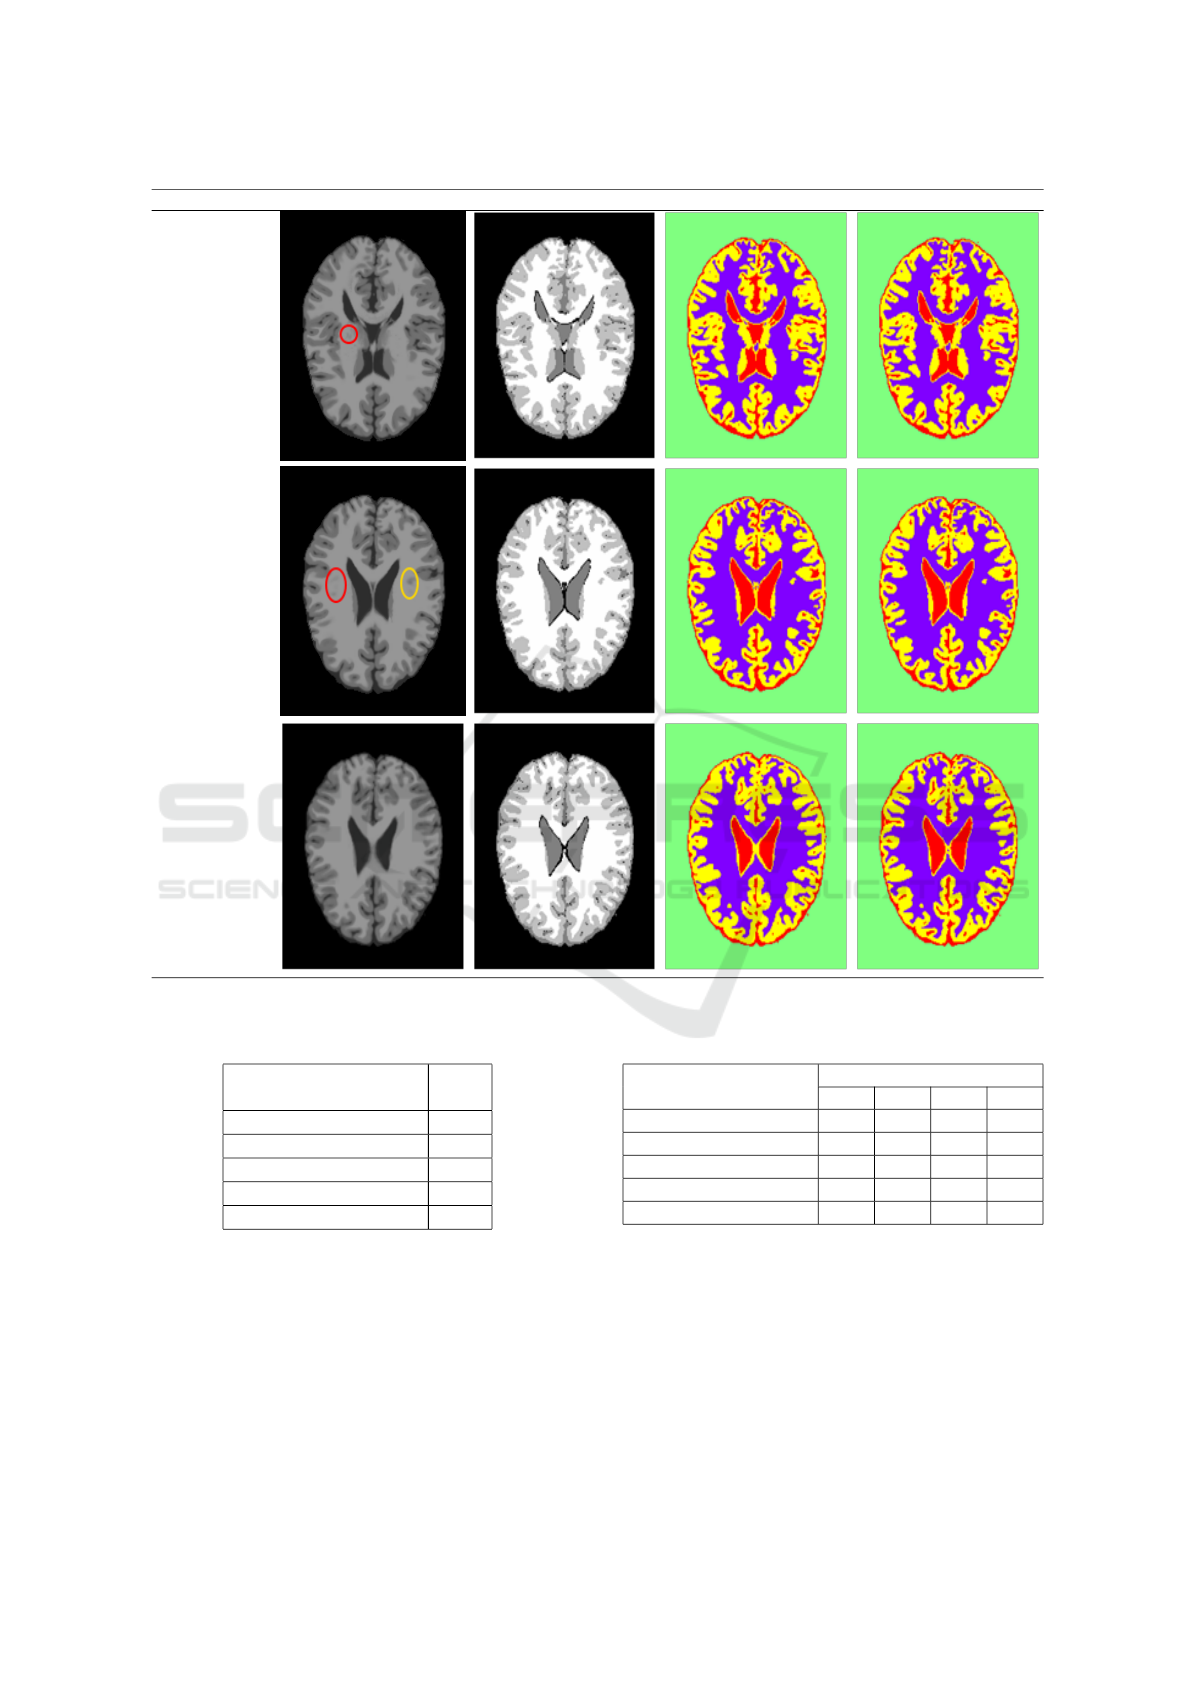

Hidden Markov Random Fields and Direct Search Methods for Medical Image Segmentation